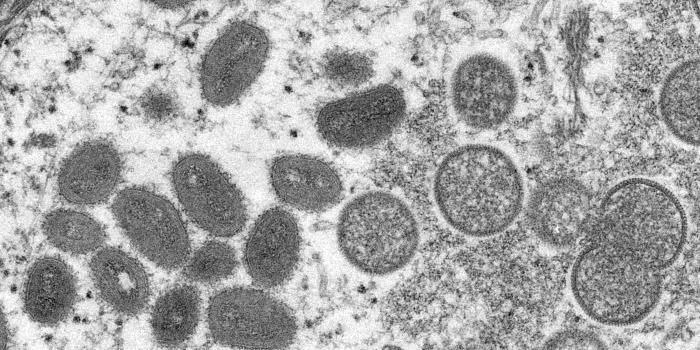

AUG 03, 2022Clinical & Molecular DXWith the 2020 Covid lockdowns still fresh in our minds, the recent outbreak of monkeypox in the United States has many p ...